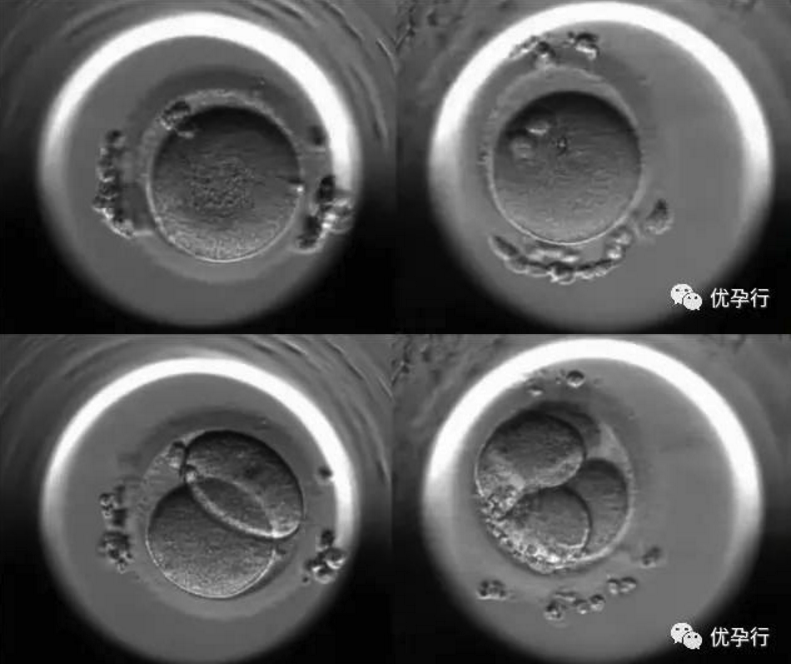

我們來看看胚胎生長的過程:

卵子和精子結合后,顯微鏡下能看到雙原核,這是它們相遇的第一天。

第2~3天,受精卵會分裂成幾個至幾十個細胞的胚胎。

到了第4天,受精卵被培育成桑葚胚,桑葚胚隨后進入高速分裂期,開始加倍分裂。

到了第5天,即成為具有一百多個細胞的囊胚。